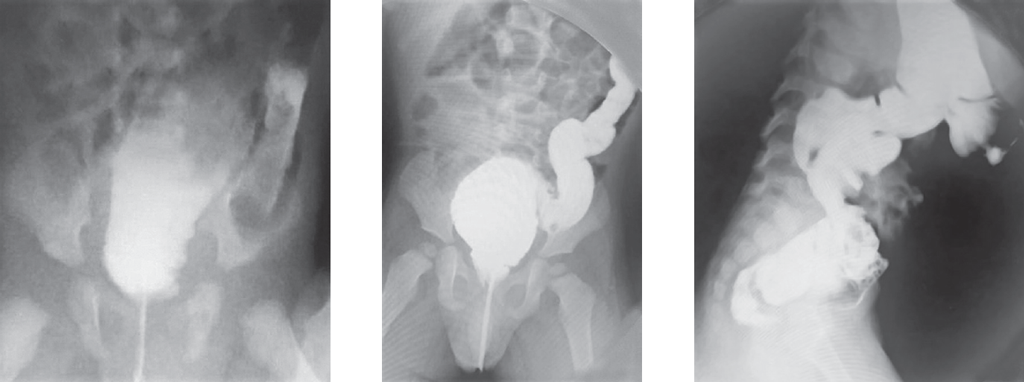

Доношенный ребенок поступил в возрасте 3 сут жизни с клиникой кишечной непроходимости: срыгивания с примесью желчи, вздутие живота, отсутствие стула. Осмотр промежности ребенка не вызвал вопросов у хирурга, по клинико-рентгенологическим данным была заподозрена болезнь Гиршпрунга. Ежедневно выполнялись очистительные клизмы. Контрастное исследование толстой кишки произведено в возрасте 14 дней жизни. По данным ирригографии выявлено резкое расширение дистального отдела сигмовидной кишки (рис. 4).

Рис. 4. Ирригография

Fig. 4. Contrast enema

Диагноз ректосигмоидной формы болезни Гиршпрунга казался очевидным и были поставлены показания к оперативному лечению. На операционном столе при попытке опорожнения кишечника выявлено затруднение при заведении газоотводной трубки. Заподозрен стеноз ануса и прямой кишки. Выполнено калибровочное бужирование, на основании которого диагноз был подтвержден. Ребенок снят с операционного стола. Болезнь Гиршпрунга была исключена. Пролечен консервативно систематическим бужированием.

Ярким примером невнимательного отношения к осмотру промежности служит случай 2 новорожденного ребенка со стенозом ануса и прямой кишки. При первичном обследовании пациента с подозрением на врожденную кишечную непроходимость можно получить много ценной информации и составить дальнейший план обследования. Задачей хирурга является не только выявление симптомов кишечной непроходимости, но и оценка правильности формирования промежности. Необходимо исключить различные варианты аноректальных аномалий — от атрезии ануса и прямой кишки с наружными свищами до стеноза ануса и прямой кишки. Признаком возможного стеноза прямой кишки может служить форма анального отверстия, располагающегося в глубине кожной воронки (рис. 7). В этом случае необходимо выполнить калибровку анального канала, который должен беспрепятственно пропускать буж № 10.

Рис. 7. Вид промежности

Fig. 7. Perineal view